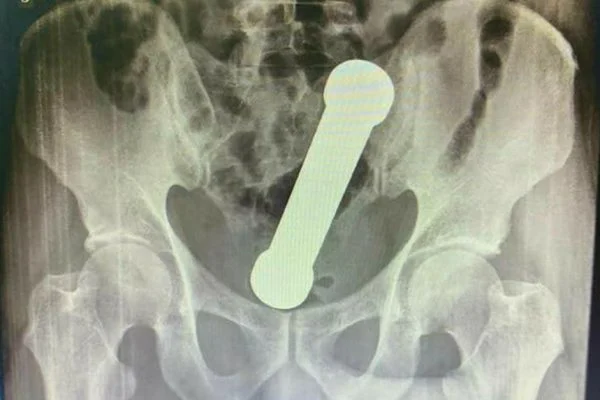

Médicos encontram peso de academia de 2 quilos dentro de pacienteReprodução

Manaus - A história de um paciente de Manaus, no Amazonas, ganhou destaque na plataforma científica International Journal of Surgery Case Reports, na última quarta-feira (6). Na ocasião, o homem procurou uma unidade de saúde relatando estar com dores abdominais e dificuldade de evacuação. Após a realização de um raio-x, os médicos descobriram que ele tinha um peso de dois quilos dentro dele.

Os profissionais de saúde tiveram que sedar o paciente para retirar o objeto, que se encontrava entre o reto e o intestino grosso. Os médicos tentaram fazer a remoção com uma pinça cirúrgica, mas como não conseguiram, a retirada teve de ser feita por um dos cirurgiões com as mãos.

Inicialmente, o homem não relatou aos médicos o que teria acontecido. Entretanto, posteriormente ele admitiu ter introduzido o peso de academia no corpo para satisfação sexual. O fato fez com que os médicos envolvidos na resolução do caso frisassem a importância dos profissionais de saúde fazerem uma abordagem cuidadosa em situações assim, já que de acordo com eles, é frequente que o paciente não revele a origem do problema devido ao constrangimento.